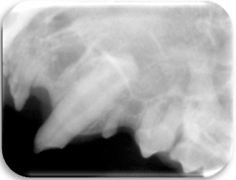

- Radiográfico (analógico y digital)

El diagnóstico clínico oral es de suma importancia ya que el plan de tratamiento y el pronóstico dependen de un certero y profundo análisis de los signos de la cavidad oral. Nuestra principal preocupación es atender los problemas que se encuentran en cavidad oral pero además siempre realizamos un detallado análisis de la función general del paciente. En nuestro centro revisamos de manera general a la mascota detectando cualquier problema sistémico. Contamos con un laboratorio de análisis clínicos en donde se realizan biometría hemática, química sanguínea, examen general de orina y pruebas para detección de enfermedades virales y de otros microorganismos. Contamos también con un laboratorio de histopatología en donde se revisa el material biológico para la detección y el diagnóstico de cambios morfológicos y lesiones en los tejidos. En lo que respecta al diagnóstico de la boca, contamos con un expediente donde se vacía toda la información dental y bucal de tal manera que mantenemos el control del tratamiento odontológico desde el inicio hasta el final y en donde el propietario o el médico que nos recomienda puede revisar en detalle toda la información recabada. Contamos con todo el instrumental y el equipo necesario para el diagnóstico de el aparato estomatognático (cavidad oral con dientes, tejidos de sostén y tejidos blandos, además de las estructuras relacionadas como articulación temporomandibular, cavidad nasal, cavidad orbitaria, etc.). Contamos con luz similar a la ultravioleta para diagnóstico de lesiones dentales por transluminación, pulpómetro para diagnóstico de vitalidad pulpar, localizador de ápices para tratamiento de conductos y equipo radiográfico tanto analógico como digital.